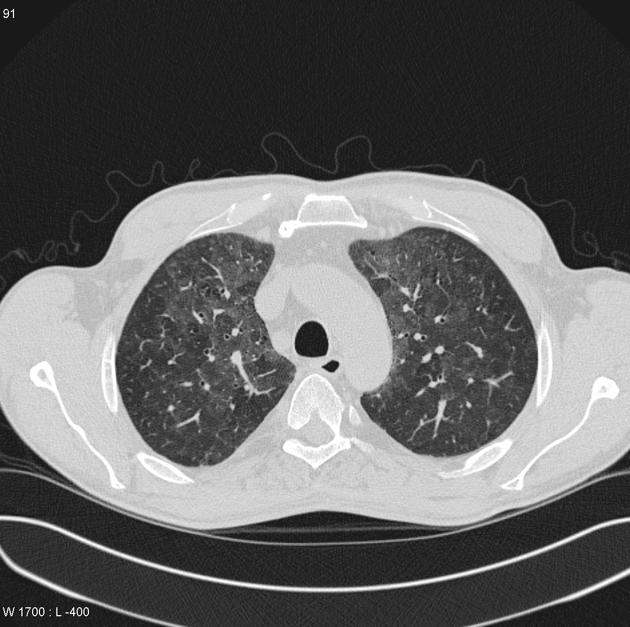

What are the three stages of congestive cardiac failure?